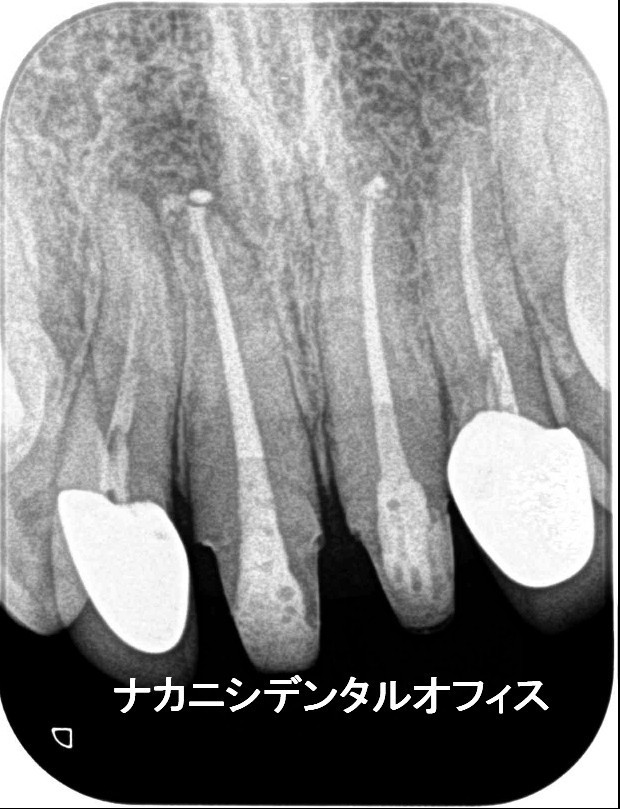

初診時に左上奥歯に冷痛と咬合痛で来院。3年前より、痛みがあったがどこに行っても原因がわからず。マイクロスコープ下で診断したところクラック(ヒビ)がはいっていました。肉眼では確認できず、レントゲンでもわかりませんでした。その日にMTAセメントでクラックを封鎖し経過観察としました。1週間後、冷痛、咬合痛は改善され、神経もとらず温存することができました。

進行した虫歯でも、当院では歯の神経を取り除かずに済む治療を行っています。必要によって、カルシウム系の成分で作られた「MTAセメント」という材料を使った治療を行います。

「MTAセメント」は、殺菌作用や歯の再生を促す特殊な素材で、虫歯が進行してしまった場合でも神経を残す治療が可能。深くまで歯を削る必要もないので、治療そのものの負担を軽減できるメリットがあります。

歯の神経を残すことは、歯の寿命を延ばし、変色などもなく見た目にも美しい歯を長く維持していくことにつながります。そのため当院ではできるだけ神経を残す治療を行い、患者さまの歯をお守りするよう努めています。

※マイクロスコープ下でのMTAセメント治療は自費診療になります。(ラバーダム下)

(33,000円~55,000円)

右上の奥歯の痛みと冷水痛で来院されました。かなり神経に近い深い虫歯になっていましたので、年齢や虫歯の状態によりマイクロスコープを使い、MTAセメントで神経の保存を行いました。後日、痛みもしみる感じもなくなり順調に経過をたどっています。